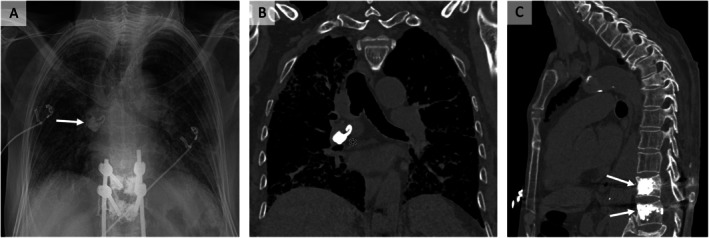

Pulmonary cement embolism is a rare complication of vertebroplasty. We report an 81-year-old man with idiopathic pulmonary fibrosis presenting with respiratory failure, 18 months post-vertebroplasty. CT revealed a hyperdense pulmonary artery embolus, underscoring the importance of vigilance for delayed vertebroplasty complications.